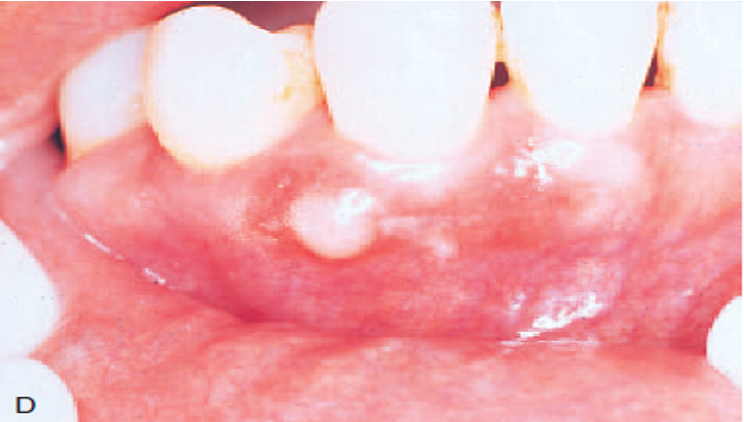

b. eruption

c. radicular

The radicular cyst is the most common cyst observed in the oral cavity. It is caused by pulpal inflammation. A dentigerous cyst forms around the crown of an unerupted or developing tooth. An eruption cyst is found in the soft tissue around the crown of an erupting tooth. A primordial cyst develops in place of a tooth, usually the third molar or posterior to an erupted third molar.